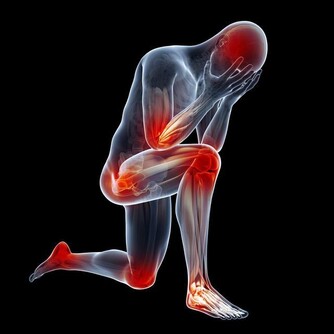

5. 脊髓型:是頸椎間盤突出或者骨贅壓迫到了脊髓,常見症狀有上下肢無力感,逐漸出現走路踩棉花感,步態拙笨甚至跌倒。後期還可出現排二便障礙。

很多人覺得頸椎病是小病,但是如果頸椎病嚴重的話,壓迫到交感神經影響到心臟,可以出現頸源性心髒病,出現心絞痛;壓迫到椎動脈,可能會急轉項時,引發忽然暈倒;壓迫到脊髓,猛地跌倒可能會造成脊髓的損傷,出現肢體癱瘓。這些都是可能的潛在危害。